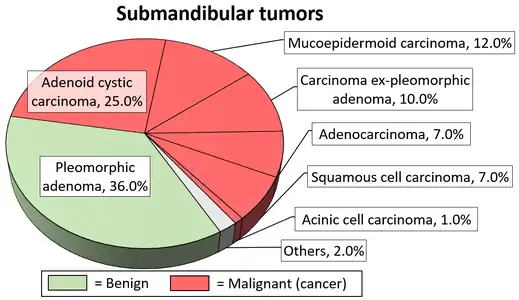

Diagrams by Mikael Häggström, MD